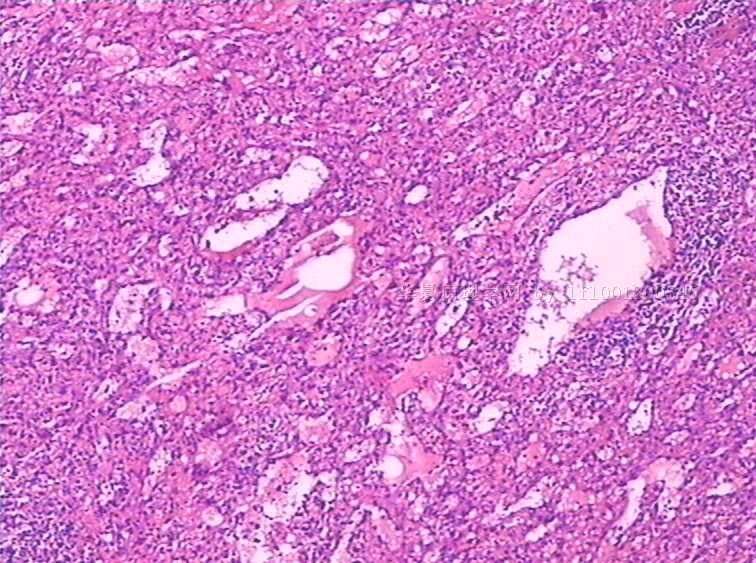

性别:

女

年龄:

49

标本名称:

反复发热,全血细胞下降1月余.CT示肝、脾肿大。骨髓检查:增生活跃,红系增高。

手术所见:脾巨大,内有梗死。肝表面光滑、肿胀。肝门淋巴结肿大,无腹水。

巨检:脾切除一个,20×15×8cm.切面灰红,有多个灰白区,最大8×6×3cm,呈楔性,小者绿豆大小

见到一些异型细胞,细胞质几乎看不到。考虑为淋巴造血系统肿瘤,脾脏原发淋巴瘤可能。

是好多组织细胞吗?期待中